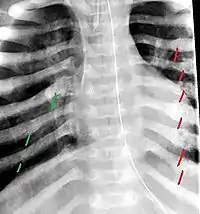

The material factual allegations of the amended complaint are as follows. Plaintiff was born on May 14, 1970. On repeated occasions during the first year of her life she was severely beaten by her mother and the latter's common law husband, one Reyes. On April 26, 1971, when the plaintiff was eleven months old, her mother took her to the San Jose Hospital for examination, diagnosis, and treatment. The attending physician was defendant Dr. Flood, acting on his own behalf and as agent of the defendant San Jose Hospital. At the time, the plaintiff was suffering from a comminuted spiral fracture of the right tibia and fibula, which gave the appearance of having been caused by a twisting force. Plaintiff's mother had no explanation for this injury. Plaintiff had bruises over her entire body. In addition, she had a non-depressed linear skull fracture which was then in the process of healing. Plaintiff demonstrated fear and apprehension when approached. Inasmuch as all plaintiff's injuries gave the appearance of having been intentionally inflicted by other persons, she exhibited the medical condition known as the battered child syndrome.

The complaint avers that as a proximate result of the foregoing negligence plaintiff was released from the San Jose Hospital without proper diagnosis and treatment of her battered child syndrome, and was returned to the custody of her mother and Reyes who resumed physically abusing her until she sustained traumatic blows to her right eye and back, puncture wounds over her left lower leg and across her back, severe bites on her face, and second and third degree burns on her left hand.